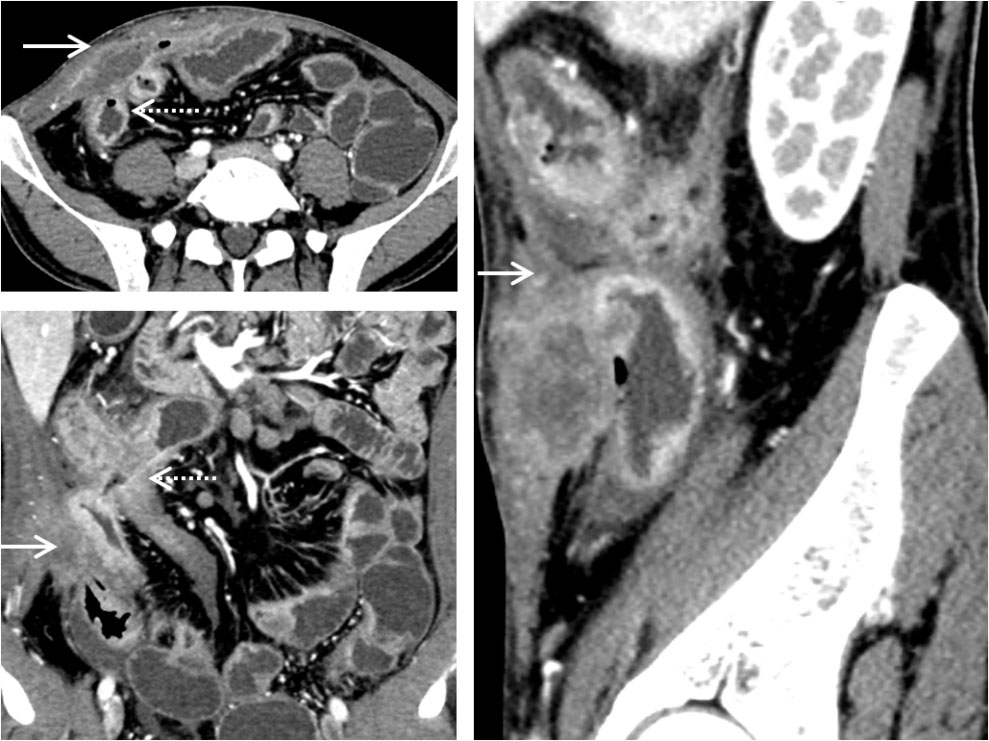

图1 克罗恩病并发脓肿 A:轴位示右前腹一梭形包块(实箭),内部为液性密度,呈环壁强化,邻近小肠肠壁增厚(虚箭);B:冠状位CT检查示脓肿(实箭)与腹壁粘连,同时合并右腹小肠肠间瘘(虚箭)形成,肠管似“花瓣”样改变,腹腔多段小肠系膜侧增厚、强化;C:矢状位CT检查示脓肿周围炎性渗出明显(实箭),局部脂肪间隙消失